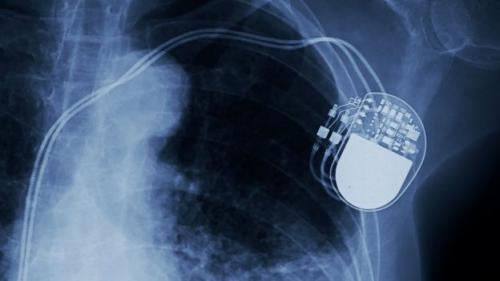

Кардиостимуляторы

Приборы для людей с аномальным сердечным ритмом появились на свет благодаря прогрессу, достигнутому NASA в миниатюризации микросхем. Если раньше человек с различными нарушениями ритма должен был постоянно наблюдаться у врача, а для восстановления ритма нужно было использовать огромные приборы, то с развитием микросхем появилась возможность создавать более компактные устройства.